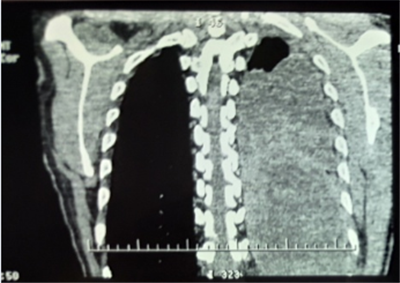

患者劉某,男性,52歲。因“胸悶、胸痛1月,發(fā)熱10余天”,就診于當(dāng)?shù)乜h醫(yī)院CT提示左側(cè)胸腔大量積液,予胸腔閉式引流同時(shí)抗感染治療,效果不佳遂轉(zhuǎn)入我院胸外科。復(fù)查胸部CT提示胸腔腫瘤合并胸腔積液。

入院后經(jīng)胸外科全體醫(yī)師對(duì)患者病情進(jìn)行綜合分析、積極術(shù)前準(zhǔn)備,于2月21日為患者實(shí)施手術(shù)治療。術(shù)中發(fā)現(xiàn)患者左側(cè)胸腔巨大腫瘤占位,體積約一個(gè)西瓜大小,幾乎完全占據(jù)了整個(gè)左側(cè)胸腔,左肺大部分被壓縮而失去功能,腫瘤與周圍組織粘連致密。切開腫物,其內(nèi)見大量魚肉樣物質(zhì)及黃色纖維素樣物質(zhì),取部分內(nèi)容物及腫物囊壁送檢冰凍切片,回示淋巴樣異型細(xì)胞。繼續(xù)游離,清除腫物內(nèi)容物,并予切除部分囊壁。

通過6小時(shí)的努力將腫瘤完全切除,出血約2000ml。術(shù)后病理檢查最終確診為胸腔尤文氏肉瘤。此種胸腔巨大腫瘤,手術(shù)難度大,術(shù)中出血多,手術(shù)風(fēng)險(xiǎn)高。